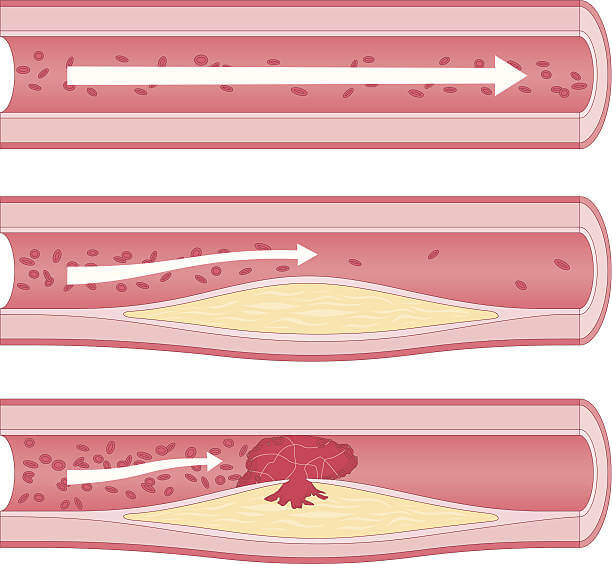

손상된 동맥 벽에 지방과 칼슘이 쌓여 혈관 내부에 플라크(동맥 벽의 지방 침착물)가 형성됩니다. 협심증과 관련된 지질 쌓임은 주로 혈액 속에 존재하는 지방인 콜레스테롤입니다. 콜레스테롤은 우리 몸에서 필요한 물질이지만, 과다하게 쌓이면 문제가 될 수 있습니다.

콜레스테롤이 혈관 벽에 쌓이면 "플라크" 라고 불리는 지방 침착물이 형성됩니다. 이 플라크는 동맥 벽 내부를 좁게 만들어 혈액 흐름을 제한합니다. 협심증은 주로 심장에 산소와 영양분을 공급하는 관상동맥에서 발생하므로, 관상동맥에 플라크가 형성되면 심장에 충분한 혈류가 공급되지 못해 협심증 증상이 발생할 수 있습니다.

플라크 형성

플라크가 점차 성장하면서 혈관 내부를 좁혀나갑니다. 이로 인해 혈액 흐름이 제한되고 심장에 산소와 영양분을 공급하는 관상동맥의 혈류가 감소합니다.

혈전 형성

플라크의 표면이 파열되면 혈소판이 그 곳에 집착하여 혈전(응고체)이 형성될 수 있습니다. 혈전은 동맥을 완전히 막을 수 있어 심장에 심각한 손상을 초래할 수 있습니다. 이렇게 동맥 경화증이 진행되면 관상동맥의 혈류가 감소하고, 심장 근육에 충분한 혈류가 공급되지 못하면서 협심증이 발생합니다.